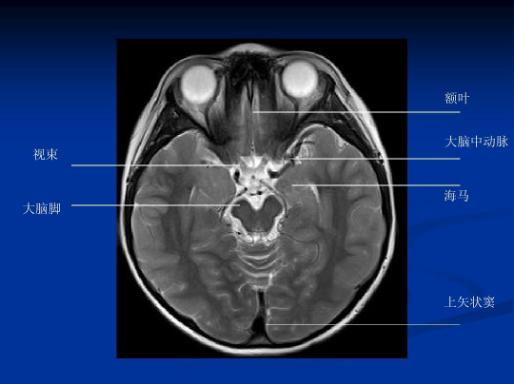

海马高清磁共振解剖及扫描方法

扫盲海马mri该如何扫描

海马结构(hf)

位置逐渐向后移内界:四脑室外界:侧脑室前内侧海马脚止于侧脑室与海马